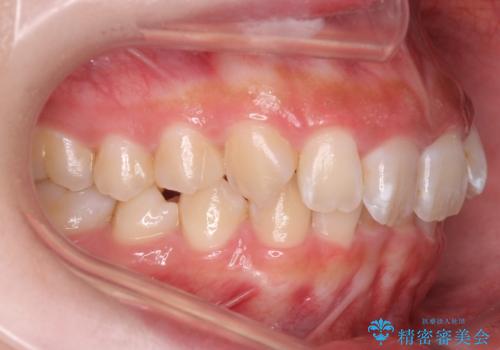

前歯の並び インビザライン 非抜歯で 深いかみ合わせの治療

- 前歯の並びを気にして来院。

上の前歯が内側に倒れこんでいました。

インビザラインで前歯の並びを整えています。

前歯の重なりが大きいいわゆる過蓋咬合を呈していましたが、ある程度適正な重なりにすることができました。